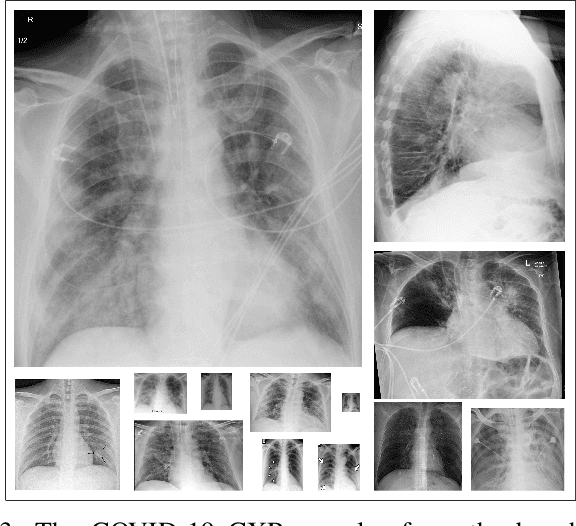

Abstract:Computer-aided diagnosis has become a necessity for accurate and immediate coronavirus disease 2019 (COVID-19) detection to aid treatment and prevent the spread of the virus. Compared to other diagnosis methodologies, chest X-ray (CXR) imaging is an advantageous tool since it is fast, low-cost, and easily accessible. Thus, CXR has a great potential not only to help diagnose COVID-19 but also to track the progression of the disease. Numerous studies have proposed to use Deep Learning techniques for COVID-19 diagnosis. However, they have used very limited CXR image repositories for evaluation with a small number, a few hundreds, of COVID-19 samples. Moreover, these methods can neither localize nor grade the severity of COVID-19 infection. For this purpose, recent studies proposed to explore the activation maps of deep networks. However, they remain inaccurate for localizing the actual infestation making them unreliable for clinical use. This study proposes a novel method for the joint localization, severity grading, and detection of COVID-19 from CXR images by generating the so-called infection maps that can accurately localize and grade the severity of COVID-19 infection. To accomplish this, we have compiled the largest COVID-19 dataset up to date with 2951 COVID-19 CXR images, where the annotation of the ground-truth segmentation masks is performed on CXRs by a novel collaborative expert human-machine approach. Furthermore, we publicly release the first CXR dataset with the ground-truth segmentation masks of the COVID-19 infected regions. A detailed set of experiments show that state-of-the-art segmentation networks can learn to localize COVID-19 infection with an F1-score of 85.81%, that is significantly superior to the activation maps created by the previous methods. Finally, the proposed approach achieved a COVID-19 detection performance with 98.37% sensitivity and 99.16% specificity.